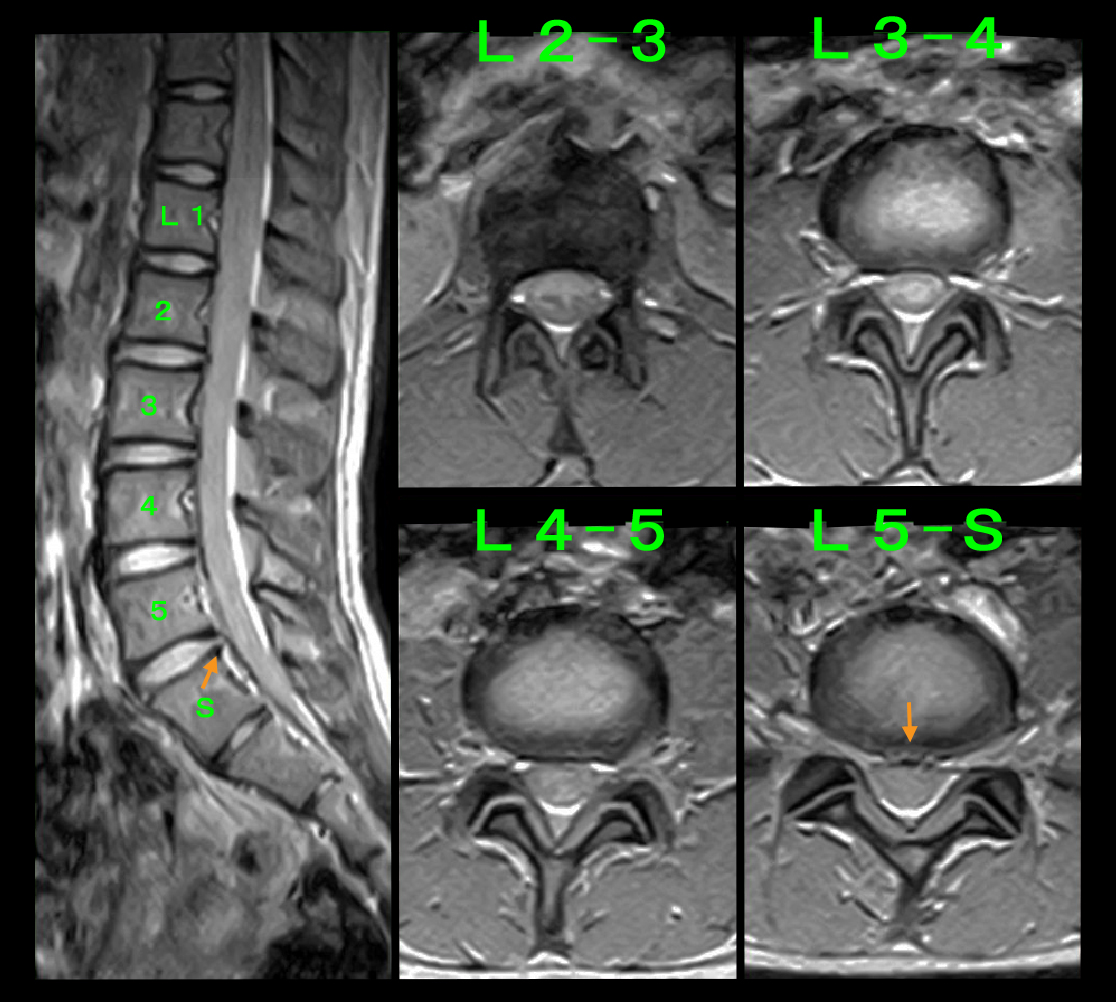

18才男 サッカー部MR2.jpg

当院では必ずMRI検査を行います。S君はL4-5高位の中等度の椎間板ヘルニアでした。スポーツ選手の腰痛は私はスポーツ障害ととらえていますが、S君にはスポーツ障害の考え方を提示しています。そして鎮痛の処方を行い、とにかく2~3週部活も体育も休みなさいと指導しました。その後練習を開始してみて、練習が可能かどうかは朝の腰痛のチェックで判断しなさいというアドバイスしました。朝の腰痛のチェックとは、①起床時の腰痛が昨日より悪化していないかどうか、②朝の洗顔時の前かがみの姿勢で腰痛が悪化していないかどうか、この2点です。腰痛があっても昨日と同等であれば練習は続けて良く、昨日より腰痛が悪化していれば、それはS君の場合には椎間板ヘルニアが悪化の傾向となっているからで、同じように練習していれば腰痛は悪化していくと判断するべきで、2~3日練習を休むか軽めの練習にするという考え方です。